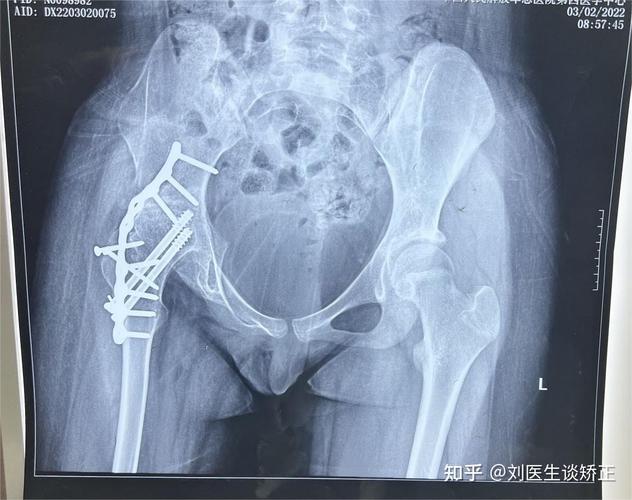

髋关节脱位

(图片来源网络,侵删)